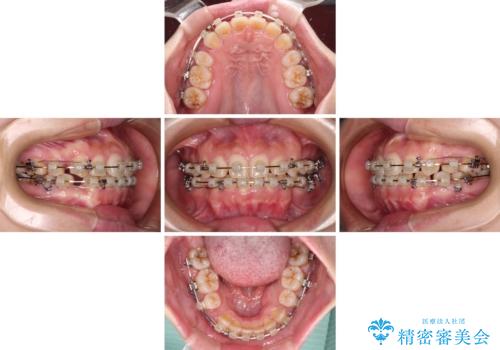

- クリアブラケット

- 治療期間

- 3年